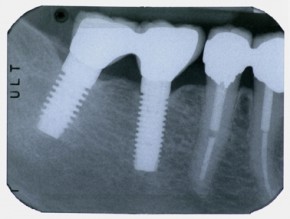

Impianti 3

Impianto unitario a livello del secondo premolare superiore destro con tecnica di mini-rialzo del seno mascellare:

- inserimento dell'impianto endoosseo sei settimane dopo la perdita in seguito ad ascesso della radice naturale, l'intervento è stato realizzato in modalità atraumatica mini-invasiva in anestesia locale, senza scollamento della gengiva, quindi senza provocare alcun dolore post-operatorio,

- dopo 3 mesi verifica dell'osteointegrazione dell'impianto, impronta e realizzazione odontotecnica di una corona unitaria in ceramica su telaio metallico.

La radiografia di controllo mostra che l'impianto, posato con una tecnica di dilatazione ossea e rialzo del seno mascellare (Soft Dilating System, pat. Arsline sa Switzerland), ha sfruttato l'intera profondità occupata dalla radice del precedente dente naturale (misurata al momento della sua estrazione). Le sue dimensioni sono adeguate per un solido utilizzo protesico.

L'osso non presenta alcuna patologia, la corona unitaria è correttamente adattata all'impianto.

L'ultima fotografia corrisponde alla situazione finale, il dente mancante è stato reintegrato in modo semplice ed autonomo, senza complicati trapianti ossei e senza dover realizzare un ponte, quindi senza dover utilizzare gli altri denti.